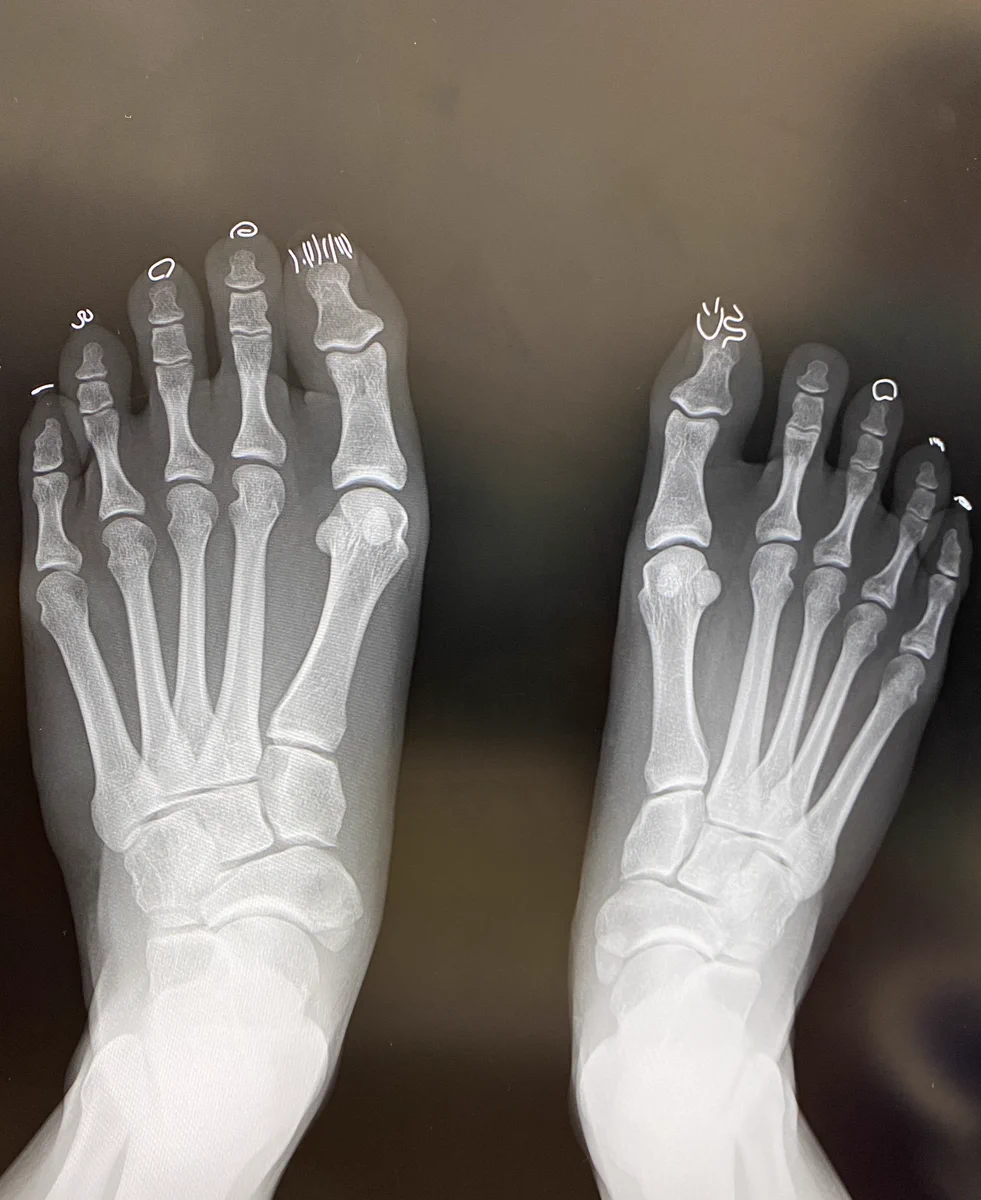

ネイルしたままレントゲンを撮った結果?ネイルが写ってしまうwww

主に女性がネイルしている人が多いですがかなり凝ったものも多く、ネイルサロンなどで自分好みのネイルをしてもらうことがあると思います。そんなネイルですがどうやらレントゲンに写り込んでしまうことがあるようでそれがこちらになります。

レントゲンにネイル写りこんじゃったわらわらわらわらわらわらわら

しかしネイルをしている人の場合、そのネイルがレントゲンに写り込んでしまうことがあるようでどんなネイルをしているかわかってしまいますねw

足の爪にどんなネイルをしているかがわかってしまうようでレントゲンに骨以外のものが写ってしまっていますねw